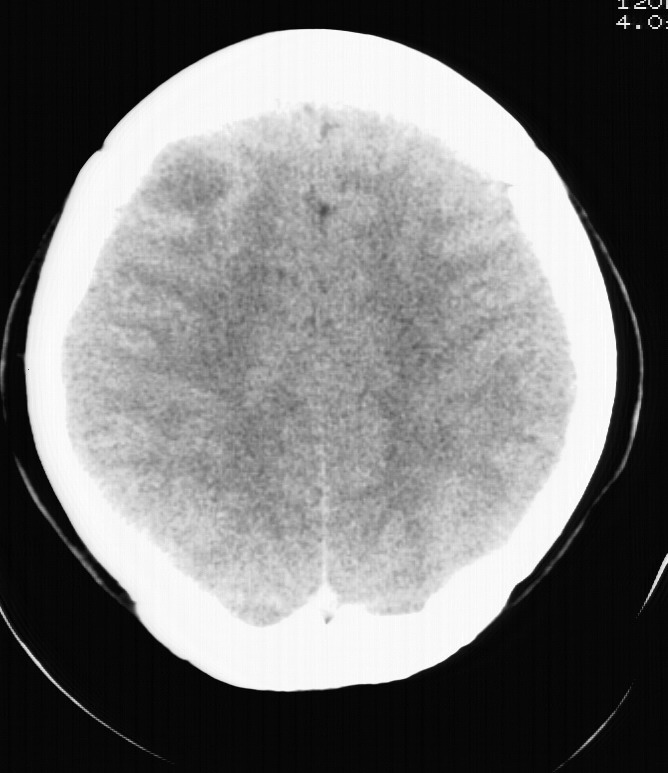

标题: CT5853:右额叶上部占位请会诊

女,34岁,自述头晕胀2年,近期感精神恍惚,无发热,实验室检查阴性。

这个患者最好做mri检查一下,排除脑外表皮样囊肿.

病灶没有明显的强化,支持囊性星形细胞瘤!不过它的形态倒是比较象肉芽肿的,还是做个mri检查吧

支持囊性星形细胞瘤!还是做个mri检查排除其它病变。